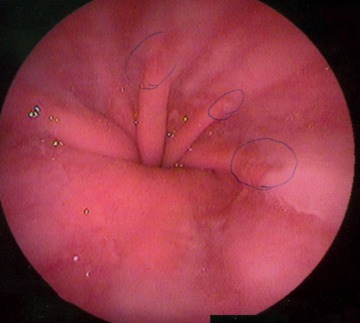

한마디로 딱 구분하자면 위내시경 검사는 카메라를 입으로 넣어 식도를 지나 위와 십이지장 그리고 소장의 시작부분까지는 볼 수 있는 검사방법입니다.

현재의 방법 중에서는 가장 정확한 검사방법입니다. 따라서 정확한 병변의 유무와 진단 그리고 내시경 검사를 하면서 바로 용종제거 등이 가능합니다. 그리고 이상하다 싶으면 바로 떼어내서 조직검사를 할 수도 있습니다.

하지만 일반 위내시경 검사를 하는 경우 내시경 즉 카메라를 삼킬 때의 구역질 그리고 몸 안에서 호스가 돌아다니는 느낌으로 인해 불편함과 불안감을 느끼는 경우가 많습니다. 그리고 수면내시경 또한 못받는 경우도 있습니다. 또한 천공이나 출혈이 있을 수 있다는 단점 또한 존재합니다.

위조영술 검사에 비해 위내시경 검사시간은 약 5분 정도로 짧은 편이며 일반내시경인 경우는 검사를 받는 사람도 직접 듣고 보면서 확인할 수 있습니다. 검사 8시간 전부터 금식해야 하고 검사 직전에 목을 국소마취하는 마취제를 마시고 30분정도 입에 물고 있어야 합니다.